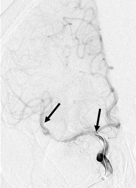

Vor allem bei besonders schweren Fällen mit Verschluss eines Gefäßhauptstamms führt diese Therapie jedoch häufig nicht zur vollständigen Heilung. Für diese Patienten besteht neben der Standardtherapie die Möglichkeit einer notfallmäßigen Wiedereröffnung des Gefäßes durch einen Kathetereingriff. Hierbei wird ein dünner Schlauch von der Leiste aus an den Verschlusses gebracht. Von dieser Stelle aus kann man mit verschiedenen Werkzeugen den Blutpfropf direkt aus dem Gefäß herauszuziehen und somit die Durchblutung des Gehirns unmittelbar wiederherstellen. Dieser Eingriff wird meist in Narkose durchgeführt. In den letzten Jahren ist die Technik der endovaskulären Gefäßeröffnung bei Patienten mit schweren akuten Schlaganfällen deutlich verbessert worden. Heute werden überwiegend stent-ähnliche Systeme eingesetzt, mit denen das Blutgerinnsel in fast allen Fällen schnell und vollständig aus dem Gehirngefäß entfernt werden kann.